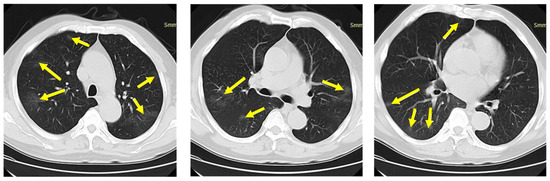

:1. Introduction